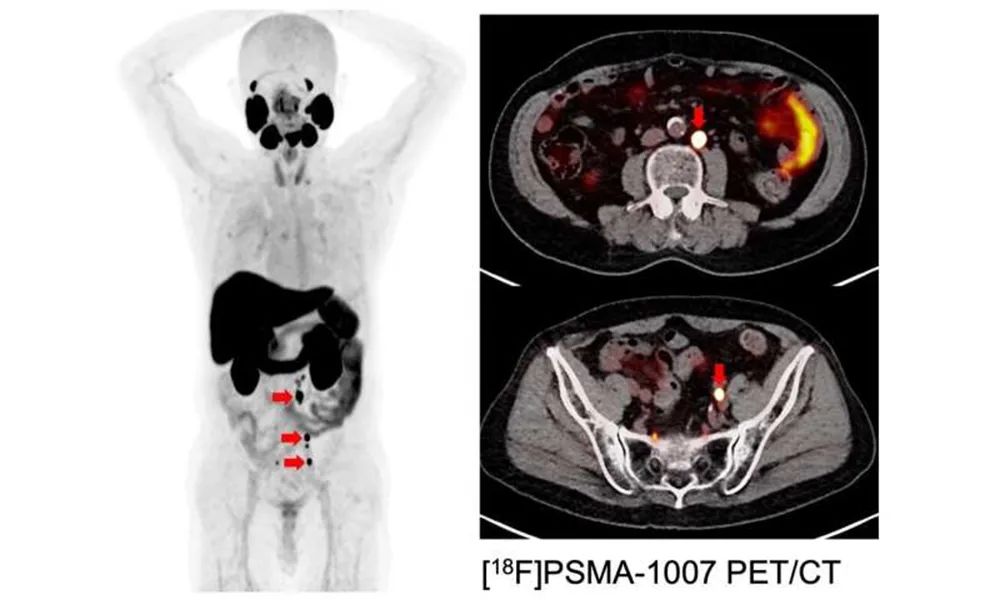

以PSMA為目標的PET圖像:激素難治性前列腺癌伴多發性淋巴結轉移(紅色箭頭)。鳴謝:渡部忠志(大阪大學)